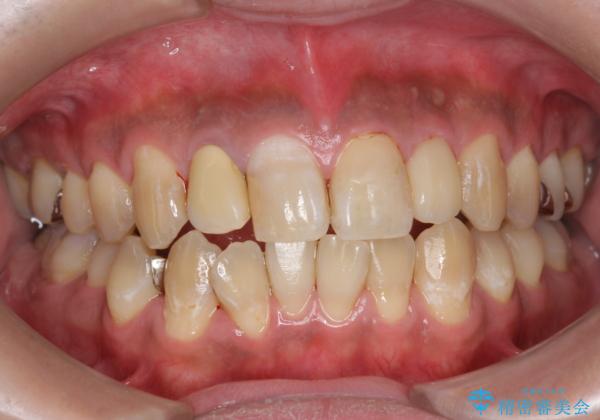

PMTC(歯科医院での専門的クリーニング)でステインを除去し白くきれいな歯に!

歯の着色だけでなく、汚れも除去し歯の表面がツルツルになったと喜んでいただけました。

横浜桜木町歯科 DH進藤